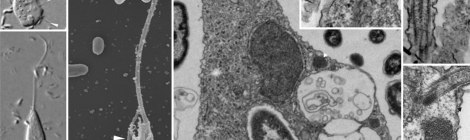

Resolvin D2 Induces Resolution of Periapical Inflammation and Promotes Healing of Periapical Lesions in Rat Periapical Periodontitis. Abstract: Periapical periodontitis results from pulpal infection leading to pulpal necrosis and resorption […]